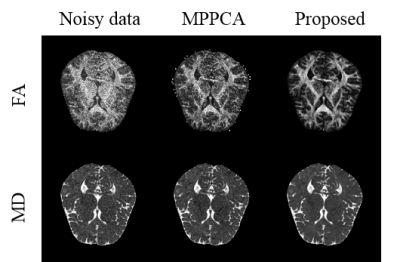

In Fig.3, the dMRI data’s diffusion gradient scheme is different from the training data. The six element maps of DTI field obtained in proposed method are less noisy with more accurate details preserved and have the lowest RMSE. In Fig 4, the real dMRI data’s acquisition scheme is different from the train data. Compared with MPPCA, FA and MD obtained in proposed method are less noisy. Both results prove that this method has a strong generalization ability.

Fig.4 FA and MD obtained from different methods. The real data has one b = 0 mm/s2 volume and 12 b = 800 mm/s2 volumes. The FA and MD of MPPCA were estimated from corresponding denoised dMRI data.